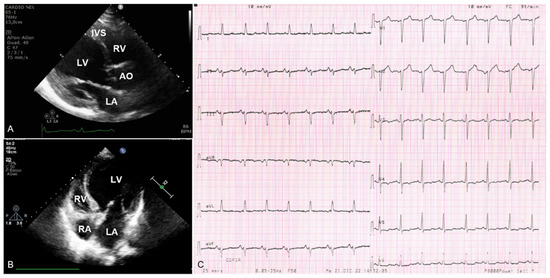

In November 2022, due to the sudden onset of shortness of breath, heartburn, and desaturation (SpO2 75%), she was escorted to the emergency room of our hospital. Her blood pressure was 140/65 mmHg, and heart rate was 84 bpm. An arterial blood gas analysis showed type 1 respiratory failure (pH 7.41, pO2 49 mmHg, pCO2 37 mmHg, SpO2 83.9%). A chest X-ray revealed a pulmonary oedema. A first-line laboratory work-up showed neutrophilic leukocytosis (WBC 12,400 u/L, neutrophils 79.8%); hyperglycemia (328 mg/dL); slightly increased high sensitivity troponins I (25 pg/mL); and increased B-type natriuretic peptide (BNP) (700 pg/mL) and D-Dimer (689 pg/mL) levels. The electrocardiogram (EKG) showed sinus tachycardia; left anterior hemiblock; and repolarization abnormalities from V4 to V6, which included slight ST segment depression suggestive of subendocardial ischemia or structural heart disease (Figure 2C). The echocardiography revealed an enlarged left ventricular end diastolic diameter (LVEDD 58 mm) and diffuse hypokinesia with severely reduced systolic function (LVEF 25%); right sections were within the normal limits; dilated (20 mm) and no collapsible inferior vena cava. Oxygen therapy and intravenous furosemide and nitrates were administered, with subsequent clinical benefit. The proband was then admitted to the cardiology unit, hemodynamically stable and asymptomatic at rest. The EKG was unchanged. The echocardiogram confirmed a dilated and spherical left ventricle, septal thinning, and severely reduced ejection fraction (LVEF 20%). Given the multiple risk factors and the clinical onset, to rule out coronary artery disease as the cause of the left ventricular dysfunction, the proband underwent coronary angiography that showed diffusely atheromatic coronary arteries without any hemodynamically relevant obstruction. A cardiac MRI was performed with the following report: “enlarged left ventricle, end diastolic volume (EDV): 263 mL, EDV/body surface area (BSA) 162 mL/m2, BSA-indexed LVEDD: 36.02 (3.6 cm/m2), apical thinning, mass augmentation (mass/BSA: 52 mL/m2), diffuse septal hypokinesia and, to a lesser extent, hypokinesia of the basal and medial regions of the anterior and inferior walls, severe depression of ejection fraction (LVEF 22%); normal extracellular volume values.; no late enhancement of contrast areas”. Based on the imaging, the proband received the diagnosis of DCM. The EKG monitoring did not show any arrhythmic episode. Heart-failure-optimized medical therapy was prescribed, and the patient was finally dismissed. At the subsequent clinical re-evaluation within one month, she was clinically stable, her New York Heart Association class (NYHA) was I–II, with referred full adherence to the prescribed medical therapy. The EKG showed a lower heart rate but it was otherwise unchanged. The echocardiogram showed a globular shaped, dilated left ventricle (LVEDD 58 mm), with septal a-dyskinesia and hypokinesia of the remaining walls; severe systolic dysfunction (LVEF 30%); a left atrium diameter at the upper limits (39 mm), but normal right sections; first degree diastolic dysfunction, with mild mitral and tricuspidal regurgitation; and sclerotic aortic root and aortic valve, with minimal aortic regurgitation. (Figure 2A,B).

Figure 2.

Echocardiographic and electrocardiographic images of the proband (III:1). (A) Two-dimensional transthoracic echocardiogram diastolic frames of parasternal long-axis view and (B) 4-chamber view showing dilated and globular-shaped left ventricle, with septal thinning. (C) Electrocardiogram showing left anterior hemiblock and slight ST segment depression from V4 to V6. LV—left ventricle; RV—right ventricle; LA—left atrium; RA—right atrium; AO—aorta; IVS—interventricular septum.